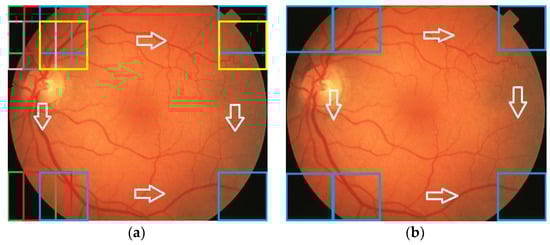

Table 5 presents the traces of all confusion matrices associated with features (the rows represent such CM traces). The fulfillment of the selection criterion for the feature-class pair (from the confusion matrices) and also the associated weights for classifiers are highlighted in gray. The last column indicates the class which uses the corresponding feature in their classifier. The features and associated weights for each RoI can be extracted from Table 5. The classifiers from Equation (12)—D1, D2, D3, and D4—were implemented taking into account the confidence intervals and band associated with the weights and the corresponding RoIs (OD, MA, EX, and HE) (Table 6). For the operational phase testing, both MESSIDOR and STARE databases were used (Figure 10). Some results concerning the box classification are given in Figure 11. The boxes classified as EX or HE have undergone a segmentation process (Figure 11, boxes labeled with SB). The results of size evaluation of EXs and HEs are presented in Table 7 and Table 8, respectively. Then, by summing the partial areas of EXs (HEs) from boxes belonging to the same image, a global evaluation in pixels and percent can be obtained (Table 9).

Figure 10.

Example of images from MESSIDOR (top) and STARE (bottom) databases for the operating phase.

Figure 11.

Results of box classification.